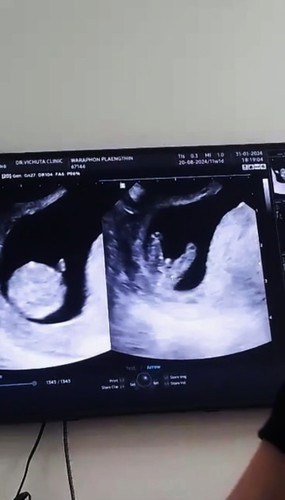

ตั้งครรภ์11+6w

โอกาสเป็นชายเยอะมั้ยคะแม่ๆ😂😍

เห็นเพศน้องแล้วหรอคะ 11วีคเอง

ไม่ทราบเหมือนกันค่ะคุณหมอบอกอาจจะเป็นชายเพราะมีอะไรโผล่

11วีค เพศยังไม่ชัดเจนคะ